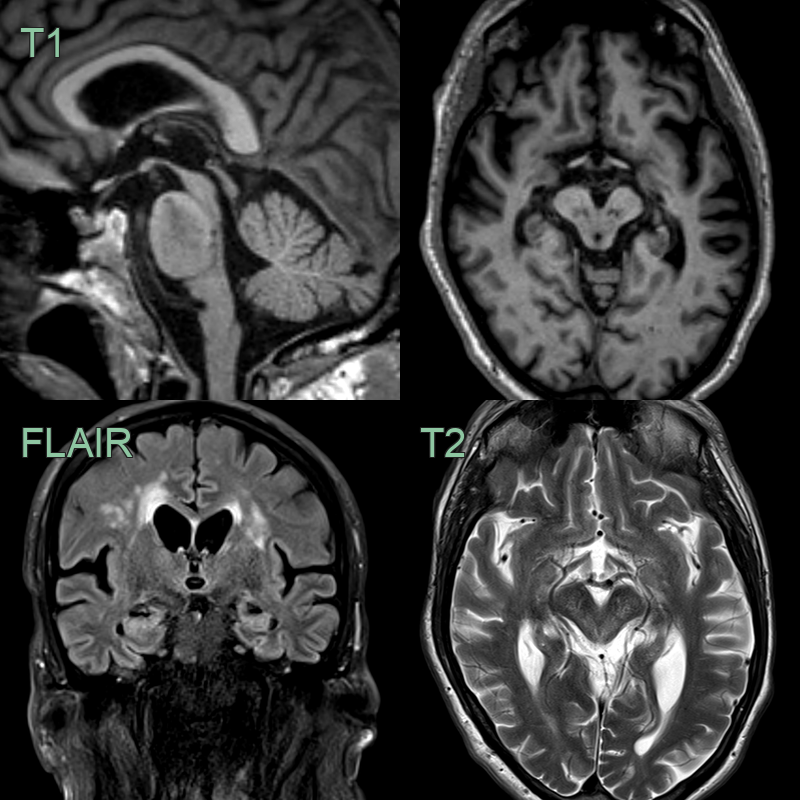

• 75-year-old patient with postural instability and supranuclear palsy.

• The midbrain tegmentum is atrophic causing a flattened superior border.

• The DaTscan shows reduced tracer uptake in the putamina (particularly on the right).